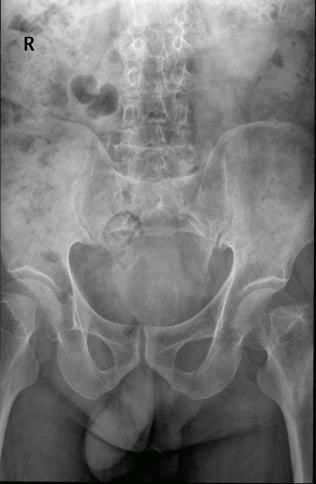

Case7:M,62y;8月前前列腺手术发现骶尾部肿物,无不适,现肿物逐渐增大,2月前伴局部疼痛。

文章插图